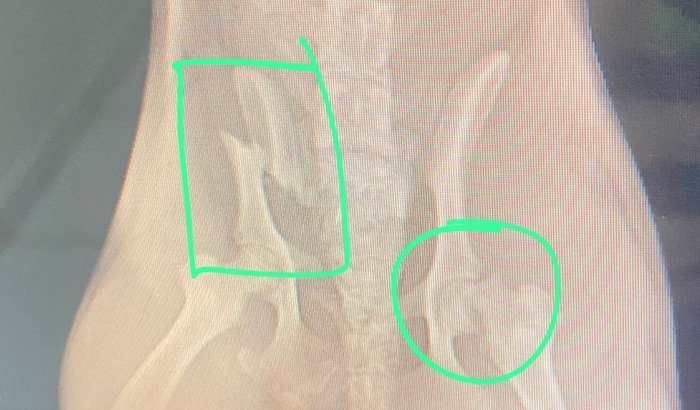

Estrela é uma cachorrinha de rua que foi atropelada e o condutor do veículo não prestou ajuda, reunimos um grupo de amigos e levamos ela a um hospital veterinário, no qual ela está internada e precisará passar por cirurgia pois teve várias fraturas, o custo do tratamento é alto e criamos a vakinha para arrecadar o valor necessário para continuarmos com os procedimentos.